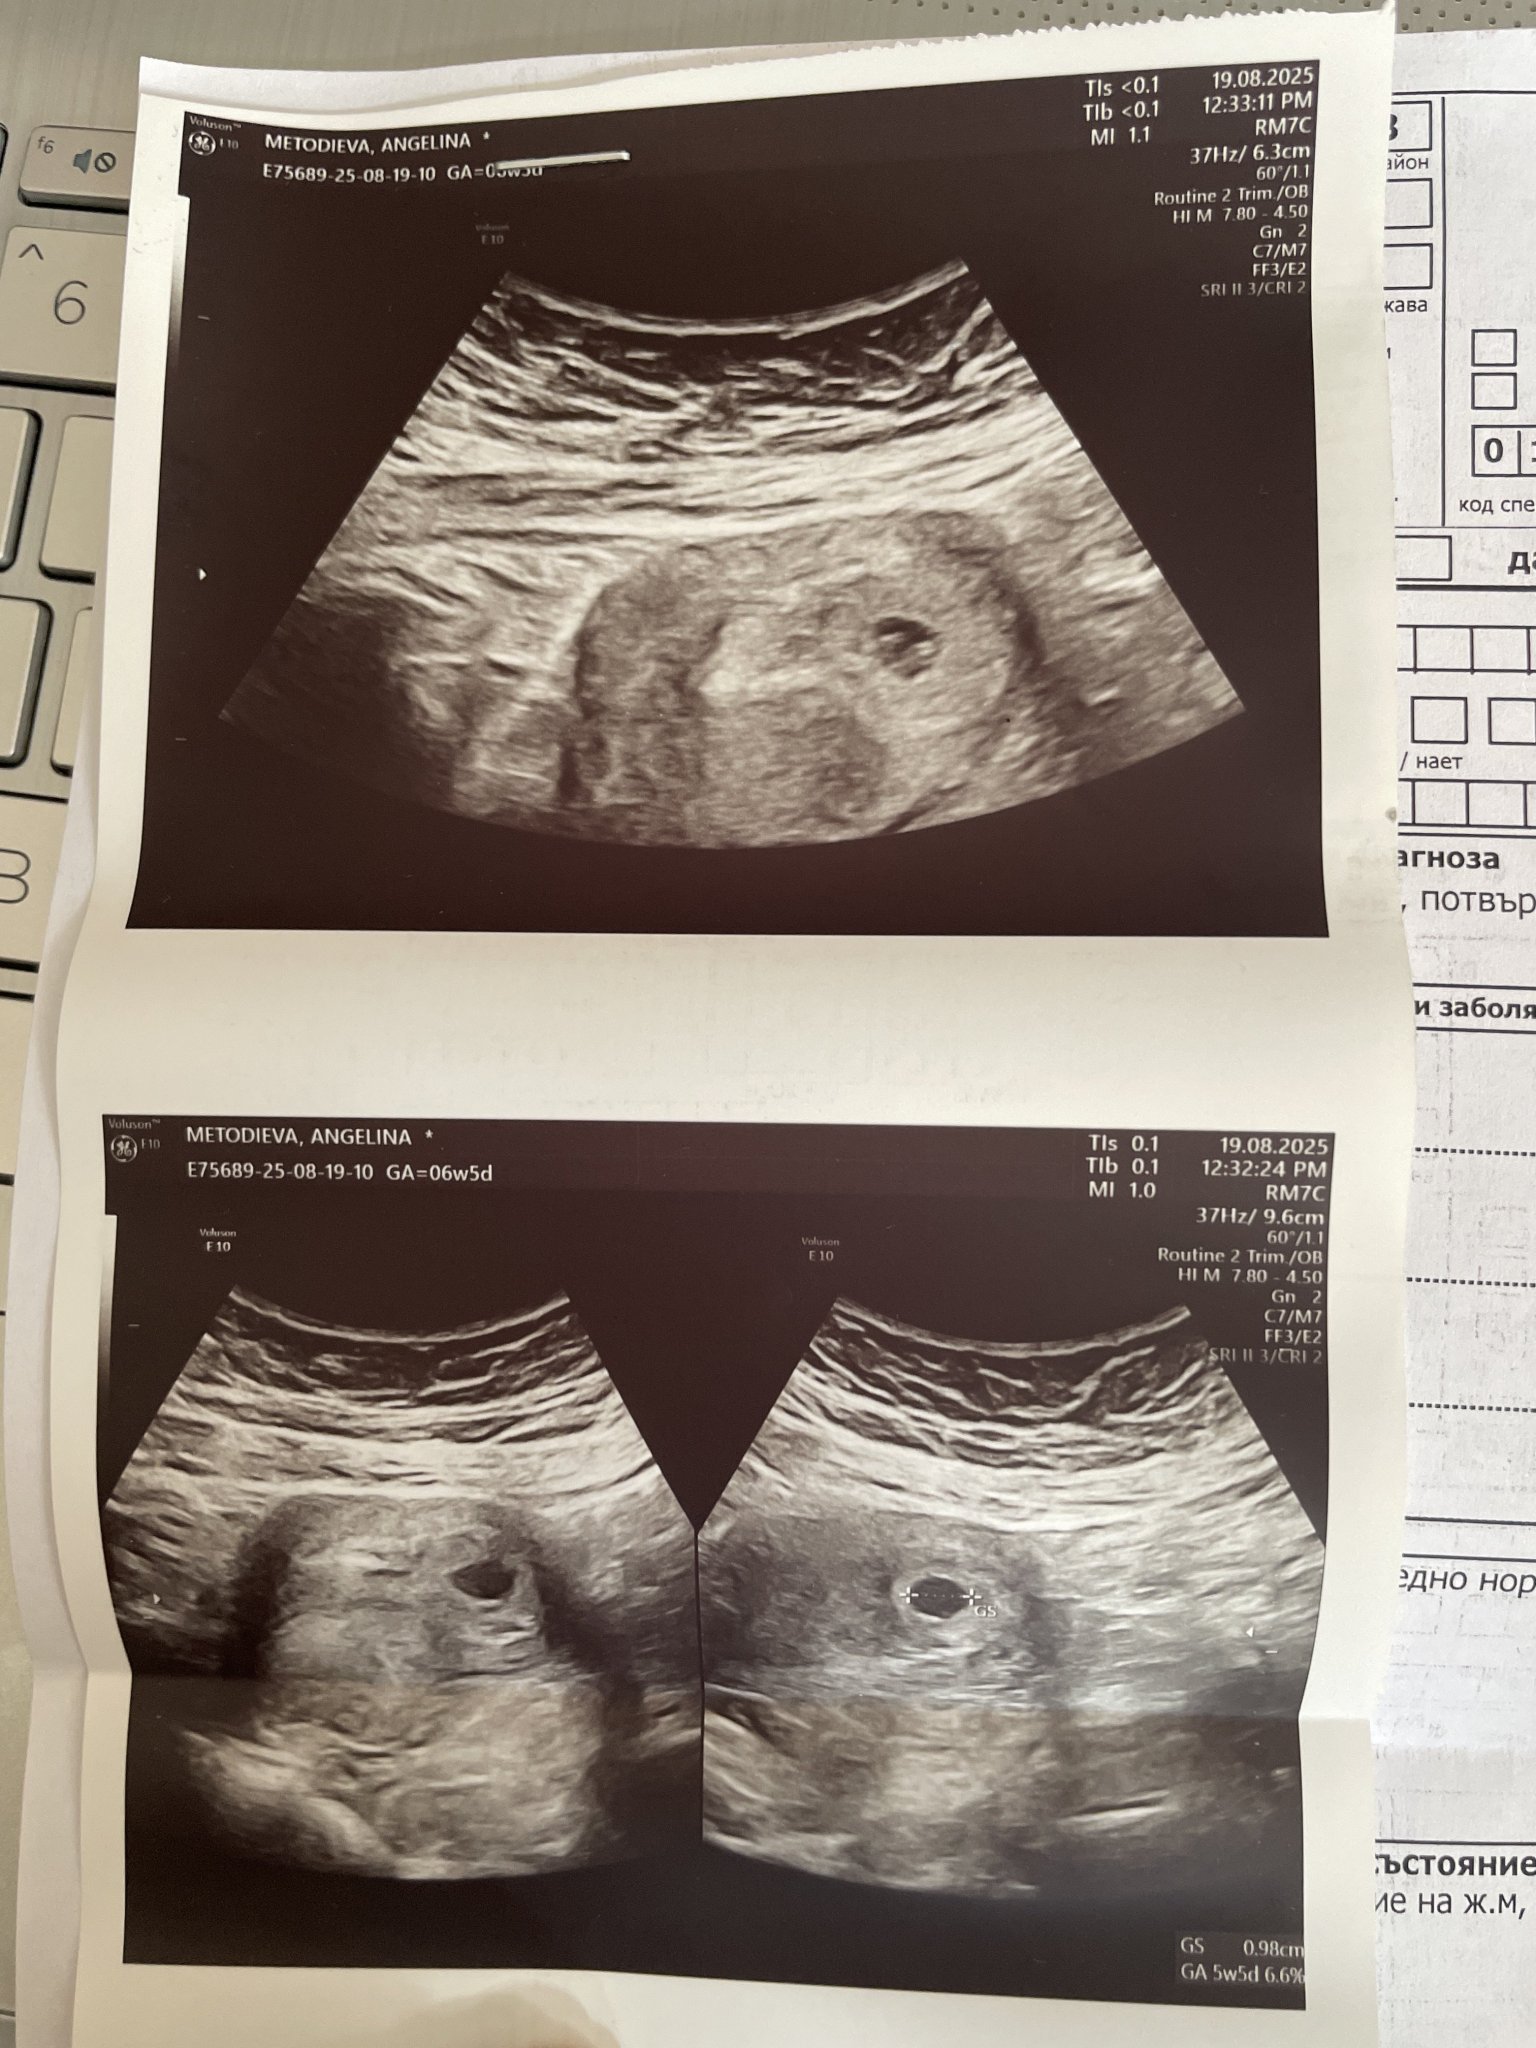

• Мнения: 2

Здравейте! Бременна съм в 6 седмица и 5 дни. Последния ми цикъл беше на 03.07.25. Имам потвърдена бременност,но според лекарката ми плода се развива добре,но сакчето му е прекалено малко. Прилагам и снимки. Въпроса ми е някой сблъсквал ли се е с нещо подобно и дали има шанс да се разшири сака. Пропуснах да кажа че съм на дуфастон и нащпа тъй като имам леко зяцапване когато се забърша след ходене по малка нужда.